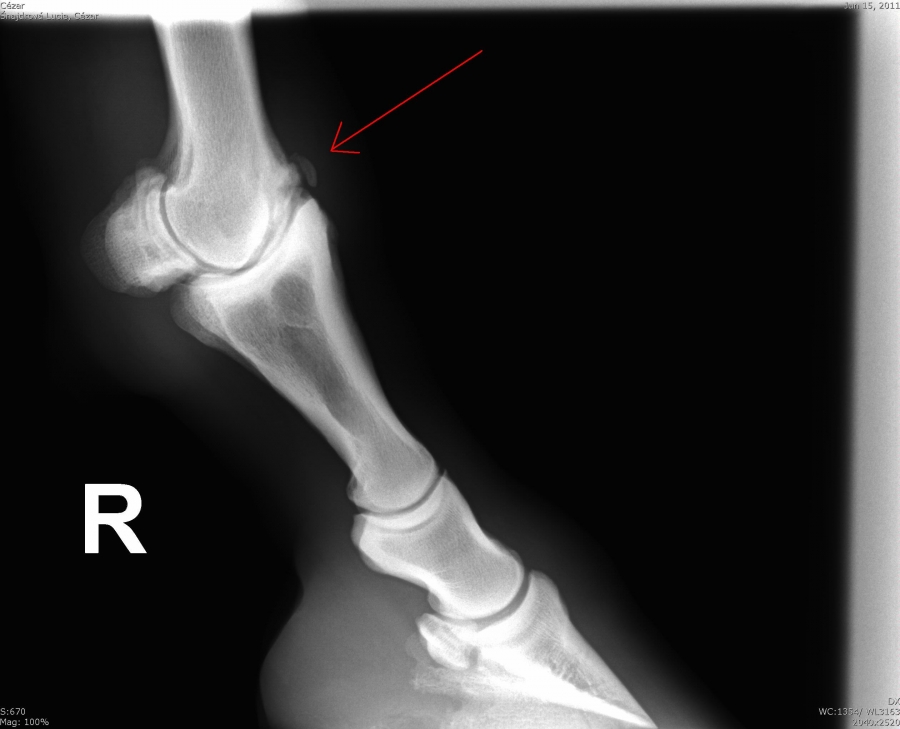

Čip ve spěnkovém kloubu na pánevní končetině

Ankylóza spěnkovýho kloubu

Fragment na spěnkové kosti